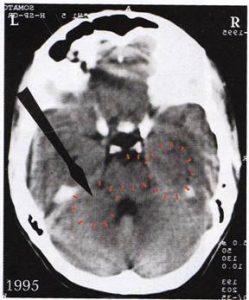

1. ábra: A felső jobb nyíl az  első szexuális konfliktusára utal a jobb oldali birtokzónában, mely másfél éves korában érte őt. A felső bal nyíl a második „szexuális konfliktus”-t mutatja (exhibicionista). Ettől kezdve a kislány skizo-nymphomániás konstellációban volt, biológiai fejlődését tekintve 8 évesen, melyet azonban a terhessége folytán 19 évesen még 3 évvel megnövelhette, így elérte a 11 évet.

első szexuális konfliktusára utal a jobb oldali birtokzónában, mely másfél éves korában érte őt. A felső bal nyíl a második „szexuális konfliktus”-t mutatja (exhibicionista). Ettől kezdve a kislány skizo-nymphomániás konstellációban volt, biológiai fejlődését tekintve 8 évesen, melyet azonban a terhessége folytán 19 évesen még 3 évvel megnövelhette, így elérte a 11 évet.

10 évesen egy szaltó ugrása közben az uszodában, amikor fejét hátul beütötte az ugródeszkába, elszenvedett egy „birtokboszankodás-konfliktus”-t és egy „esés-konfliktus”-t. Egyébként lehet látni mindkét kamra hátsó szarvában a Hameri gócot, a jobb agyféltekén a bal (partnert érintő) petefészket a megoldási fázisban petefészekcisztával, a bal agyféltekén a gyermekre vonatkozó, még aktív Hameri gócot. A két alsó nyíl a „nyakba szakadó konfliktus” reléjére mutat. A Hameri gócok félig aktív, félig megoldási fázisban vannak (= függőben lévő gyógyulás).

2. ábra: A bal oldalon látható nyíl ugyanarra az exhibicionista által okozott „szexuális konfliktus”-ra utal. Látható a góc körüli a halvány ödémperem. Mivel a páciens a birtokbosszankodást / eséskonfliktust időközben már megoldotta, feloldhatóvá válhat végre a bal féltekei Hameri góc, mely ugye másodikként csapódott be. Úgy tűnik azonban, hogy ezen még nem tudta magát túltenni, mert jelenleg a nigériai barátjával nézeteltérései vannak, melyek ezen a sínen futnak. Így a „szexuális konfliktus”-a soha nem kerül igazán feloldásra.